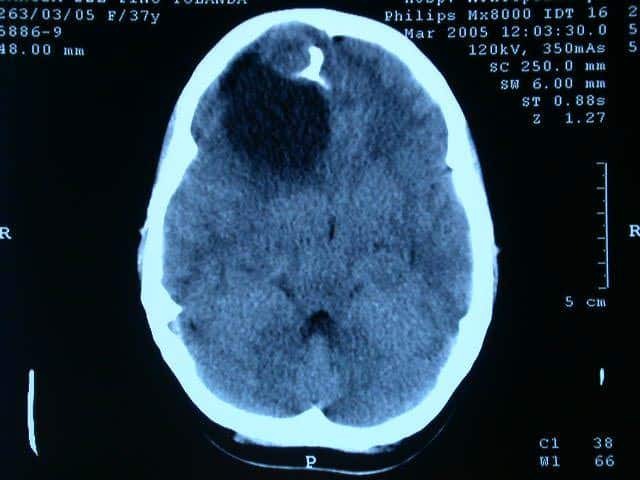

• primera imagen tomografica

primera imagen tomografica

esta se logra en un paciente con tumor quistico circular en el lobulo frontal.

• primer prototipo de escaner

primer prototipo de escaner

Sir Godfrey N. Hounsfielduna crea una nueva y diferente forma de obtener y registrar la interacción de los Rayos X con el cuerpo. De esta forma pudimos visualizar los distintos órganos y tejidos, con el giro el tubo en el eje axial y procesamiento de la información con detectores y amplificadores de mayor sensibilidad que la placa radiográfica convencional disponible hasta ese momento.